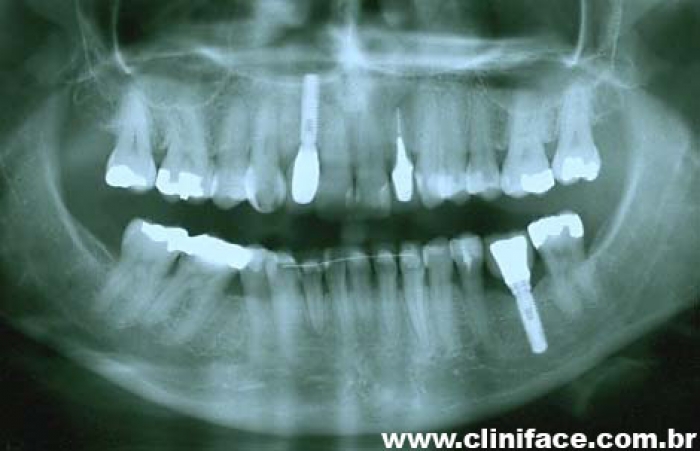

Imagem inicial e final de caso de agenesia dental, reabilitado com implante unitário no elemento 12

Raio X mostrando agenesia do elemento 12, reabilitado com implante e prótese fixa em porcelana